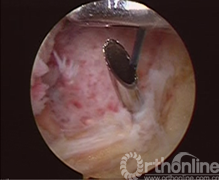

试复位成功后,于胫骨结节内1cm处做2~3cm小切口。Stryker前交叉韧带(ACL)胫骨瞄准器65°角定位骨隧道内口。其位于胫骨髁间隆突骨折创面后缘正中,外口定位于胫骨结节内下方,用1.8~2.0mm钻头钻取骨隧道后,拔出钻头,过该隧道插入18号硬膜外穿刺针,用刮勺向下压ACL体部使穿刺针穿ACL体部露头(图2)。沿针管插入PDS-Ⅱ0号可吸收线做牵引线关节内穿出,从前内侧入路牵出关节(图3)。若该针不能顺利地从ACL体部穿出,可用穿刺针自前内侧入路穿入ACL体部,自针管穿线过ACL体部,线的关节内部分与胫骨髁间隆突骨折床后部穿出骨隧道的线的未端打结连接,形成接力完成穿线过程。然后用两把止血钳分别固定该牵引线的两端。同法用前交叉韧带(ACL)胫骨瞄准器50°于胫骨创面前缘正中钻孔,PDS-Ⅱ0号牵引线于关节内穿出,自前内侧入路牵出,同样用止血钳固定两端备用。取一根长PDS-Ⅱ0号线两端自身打结做形闭环、再将环拉紧成袢形双线。分别将自前内侧入路出关节的牵引线与双线的袢形两端打结,牵拉牵引线的胫骨隧道侧,将双线拉入关节形成前后方向的袢形固定骨块(图4)。同法可于胫骨创面的两侧缘中间再钻一组骨隧道,同法引入双股PDS-Ⅱ0号横形固定骨块,固定线的未端自胫骨隧道外口引出。于胫骨结节内侧切口下方与胫骨干近端成锐角拧入一枚带垫片的空心螺钉(图5),螺钉先不拧到底。拉紧两组固定线,做后抽屉试验动作,关节内两组双线成“十字”交叉,探针探查复位状况。解剖复位后,将线拴桩捆绑于的螺钉上,此时将螺丝钉拧紧,螺钉旋进时产生很大的拉力将再次拉紧固定线,使骨块牢固固定。关节内两根双线成“十字”交叉,线绷的很紧固定非常有力。螺钉拧紧后即完成解剖复位和固定。

图3 图4